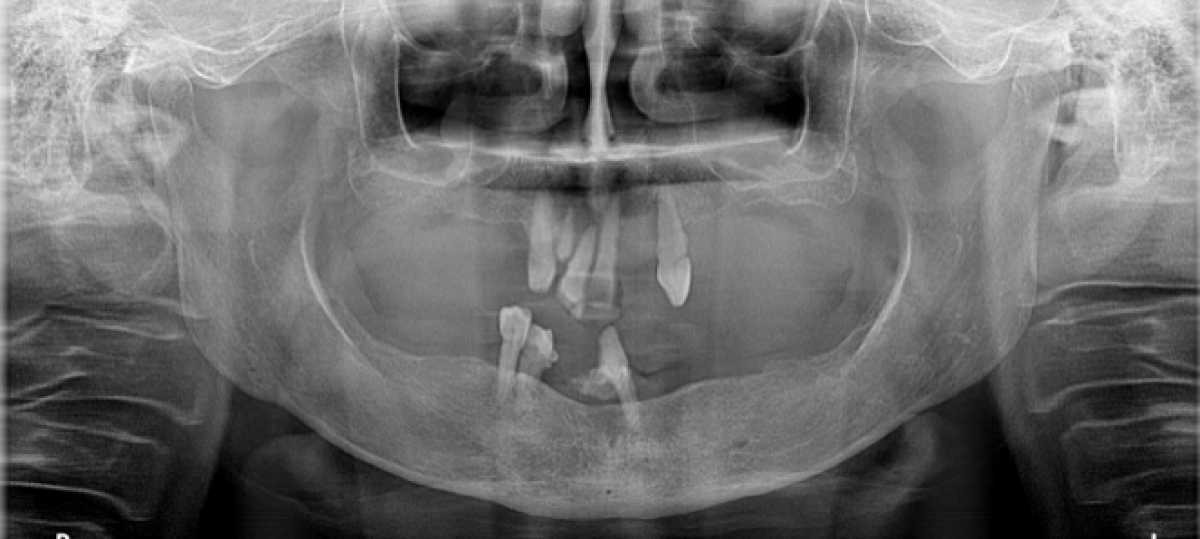

A 63-year-old female patient, smoker, in good general health, with severely compromised dental arches.

X-ray examination with orthopantomography showed severe periodontal disease in the few remaining teeth in the arches and significant bone resorption in the maxilla, resulting in a severe loss of vertical dimension. Cone Beam CT is required in order to establish a proper treatment plan. (PICTURE 1,2)